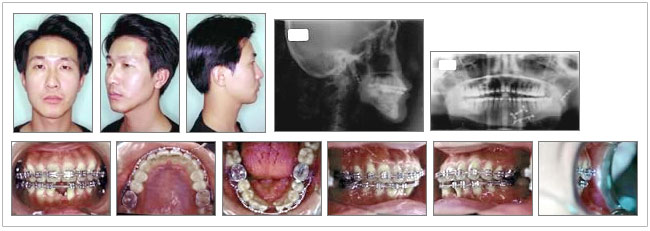

患者: 男性

年齡: 27Y07M

Dental stage: ⅣC

主訴: 牙齒完全沒有辦法咬東西

過去病史: 患者於2000年5月間發生車禍導致左側mandibular body fracture及subcondyle fracture,送醫後經中部某私人綜合醫院之整型外科為其進行下顎接合手術,手術除了以mini-plate及screw作fixation之外,據患者所言,當時還並用了口腔外的固定裝置,所以才在顏面的左側留下了一些疤痕。術後患者發覺牙齒完全無法咬合,以致進食相當困難,輾轉經人介紹來到本院,當時口腔外科醫師也有建議再次以手術的方式為患者重建咬合,唯患者已視手術為畏途,於是轉診至齒顎矯正科進行會診。

一、 口腔外檢查

1. 正面觀:左右不對稱,chin向右偏移。

2. 側面觀:Straight facial type

3. 顏面的左側有一些疤痕。

二、 口腔內檢查

1. 咬合相當不穩定,整體的Open bite,很難以一般的咬合分類法為其做分類。

2. 下顎窄縮,兩側的molar及premolar均向舌側傾倒。

3. #15 Linguoversion

4. #33 & #41 Missing

5. Overbite:-1.0mm

6. Overjet:+3.0mm

三、側面測顱放射X光片分析

1. Skeletal ClassⅠ:正常的∠ANB

2. Upper incisor及lower incisor的角度均為正常

3. 美觀線的分析亦屬正常

四、環口放射X光片分析

1. Left subcondyle fracture

2. Left mandibular body facture,fracture line經過經過#33處,#33 missing,#32及#34牙根傾斜。

3. #15 Space insufficiency

◆ 治療結果

一、 治療時間:1年3個月

二、 顏面外觀

1. 相較於原先不甚樂觀的治療目標訂定,正面的對稱性有得到些許的改善。

三、口腔內

1. occlusal interference已完全去除

2. 上下顎建立了一個normal arch form

3. interdigitation重建

4. 得到一穩定的咬合

四、側面測顱放射X光片分析

維持了原有的Skeletal ClassⅠ、正常角度的Upper incisor及lower incisor、正常的美觀線分析。

五、環口放射X光片分析

1. #32及#34牙根平行度獲得重建

2. #15獲得正常的alignment